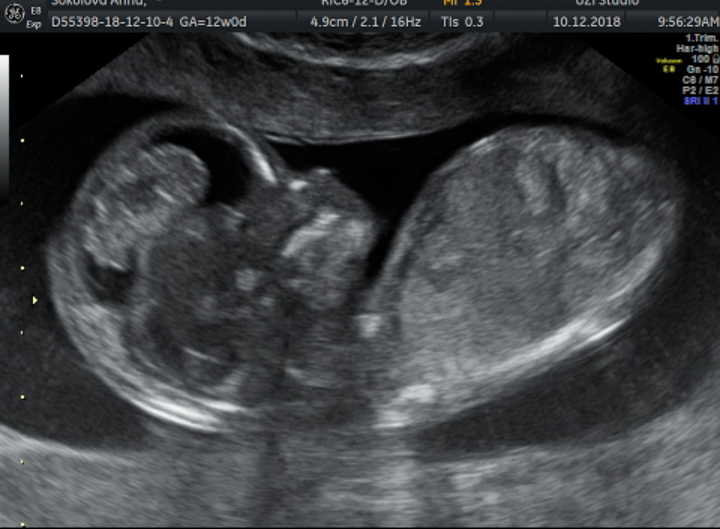

Наш 1 скрининг в 12 недель ♥️

Всё о нашей беременностиНаконец то дождались 1 скрининга, все у нас хорошо)) ттт🙏узистка сказала 70 % что будет девочка, я счастлива, муж сказал что все равно надеется что будет сын) мы ходили вместе, сказал что он успел разглядеть там пипеньку😂все узи крутилась, отварачивалась,закрывала лицо ручками))ну или закрывал))

Подскажите сколько у малыша КТР на этих фото? Мне через неделю тоже скринг предстоит, хочу сравнить. И это Вы 3д узи делали? Так четко видно всё, я сегодня УЗИ делала, всё сливается в один серый фон, правда мы еще 44мм по КТР

Спасибо) да это у нас узи студия, там и 3д и обычное узи делают за раз в разных режимах смотрят)) у нас ктр не очень большой 4.9, мы на 2 дня немножко отстаем в размере)